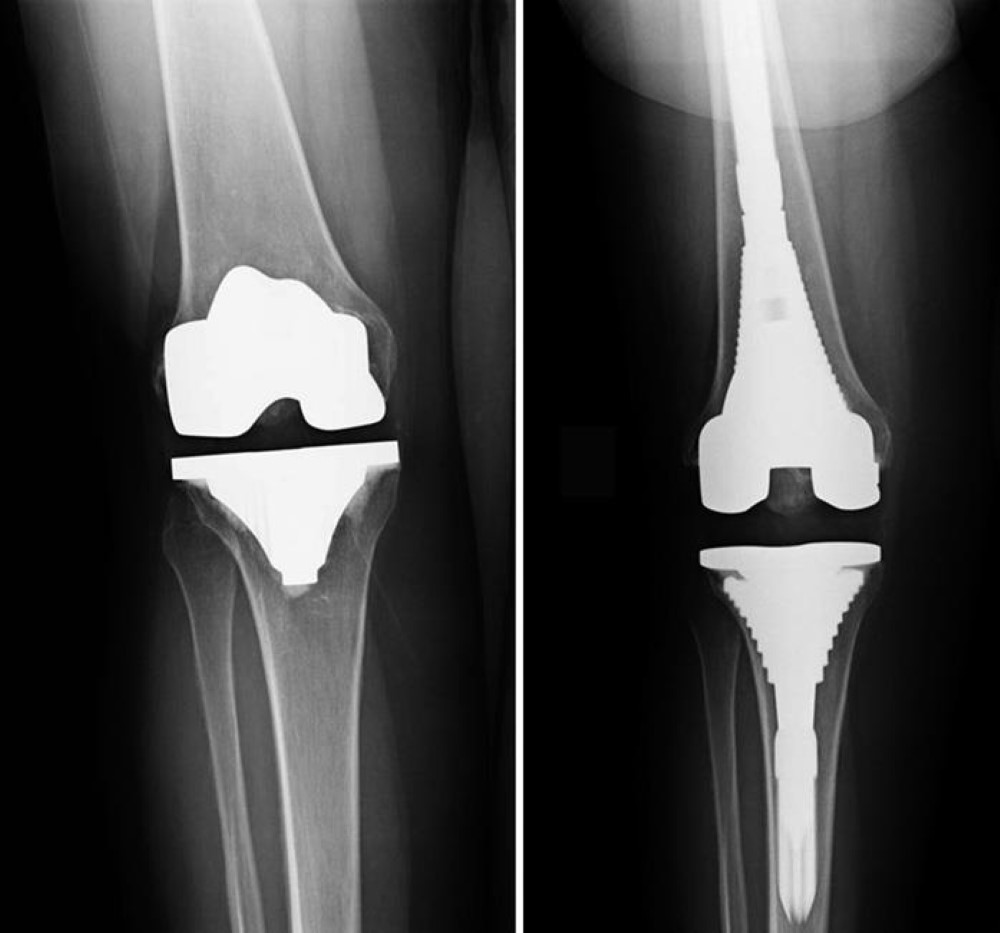

Knee revision surgery. About Knee Replacement Revision Knee Replacement Surgery also known as knee arthroplasty is a surgical procedure in which the damaged parts of the kneecap thighbone and shinbone of the patient are replaced with artificial parts. Knee revision surgery which is also known as revision total knee arthroplasty is a procedure in which the surgeon removes a previously implanted artificial knee joint or prosthesis and replaces it with a new prosthesis. In this procedure the doctor will put the patient under regional or general anesthesia.

Revision surgeries require extensive planning and may require special implants and tools. Albeit the present inserts are intended to last numerous years its conceivable Knee Replacement Statisticsthat s. A knee revision is the replacement of prosthetic implants in a person who previously had a total knee replacement.

Additionally knee replacement revision surgery can be used to correct injury caused to the knee from side effects of the device. Revision total knee replacement is more complex and takes longer to perform than primary total knee replacement. A Revision Total Knee Replacement occurs when a Total Knee Replacement Knee Arthroplasty has failed due to factors such as incorrect surgical technique or.